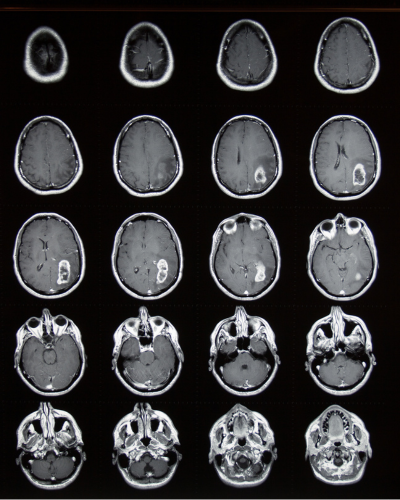

Par exemple, lors d’une IRM cérébrale, une tumeur peut apparaître en hypersignal après injection de gadolinium. Dans une IRM hépatique, le produit de contraste permet de mieux distinguer des métastases hépatiques. En IRM mammaire, il aide à détecter des lésions suspectes lorsque la mammographie est insuffisante. Enfin, en IRM vasculaire, il met en évidence des anévrismes ou des sténoses artérielles, améliorant considérablement la détection des maladies cardiovasculaires.